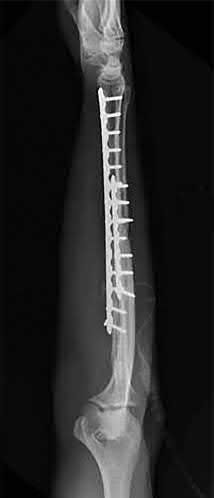

Question 19:

A 28-year-old male sustains a closed comminuted tibial shaft fracture. Two hours post-injury, he develops severe leg pain unyielding to narcotics. His blood pressure is 120/80 mmHg. Intracompartmental pressure monitoring is performed. Based on current guidelines, which measurement dictates an emergent 4-compartment fasciotomy?

Options:

- Absolute compartment pressure > 20 mmHg

- Absolute compartment pressure > 25 mmHg

- Delta pressure (Diastolic BP - Compartment Pressure) < 30 mmHg

- Delta pressure (Systolic BP - Compartment Pressure) < 30 mmHg

- Delta pressure (Mean Arterial Pressure - Compartment Pressure) < 40 mmHg

Correct Answer: Delta pressure (Diastolic BP - Compartment Pressure) < 30 mmHg

Explanation:

Acute compartment syndrome is classically defined by tissue hypoperfusion. The absolute compartment pressure is less reliable than the differential pressure (Delta P). A Delta P (Diastolic Blood Pressure minus Compartment Pressure) of less than 30 mmHg is an absolute indication for emergency fasciotomy, as capillary perfusion gradient is lost when tissue pressure approaches the diastolic pressure.